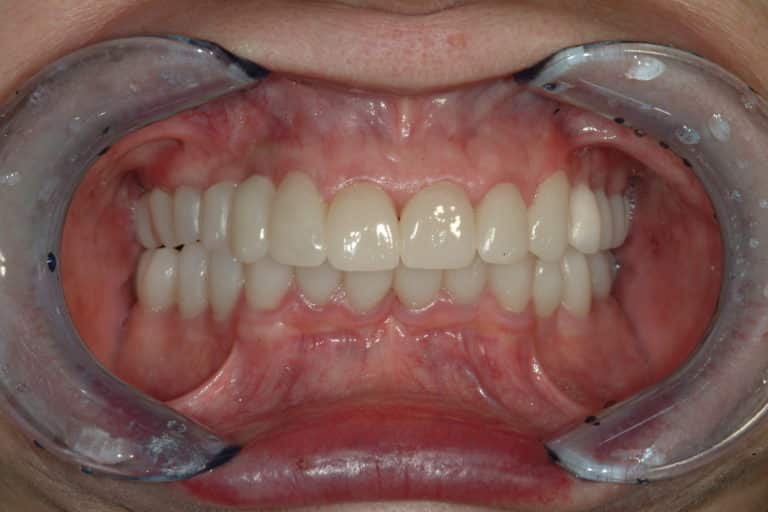

Before & After Gallery